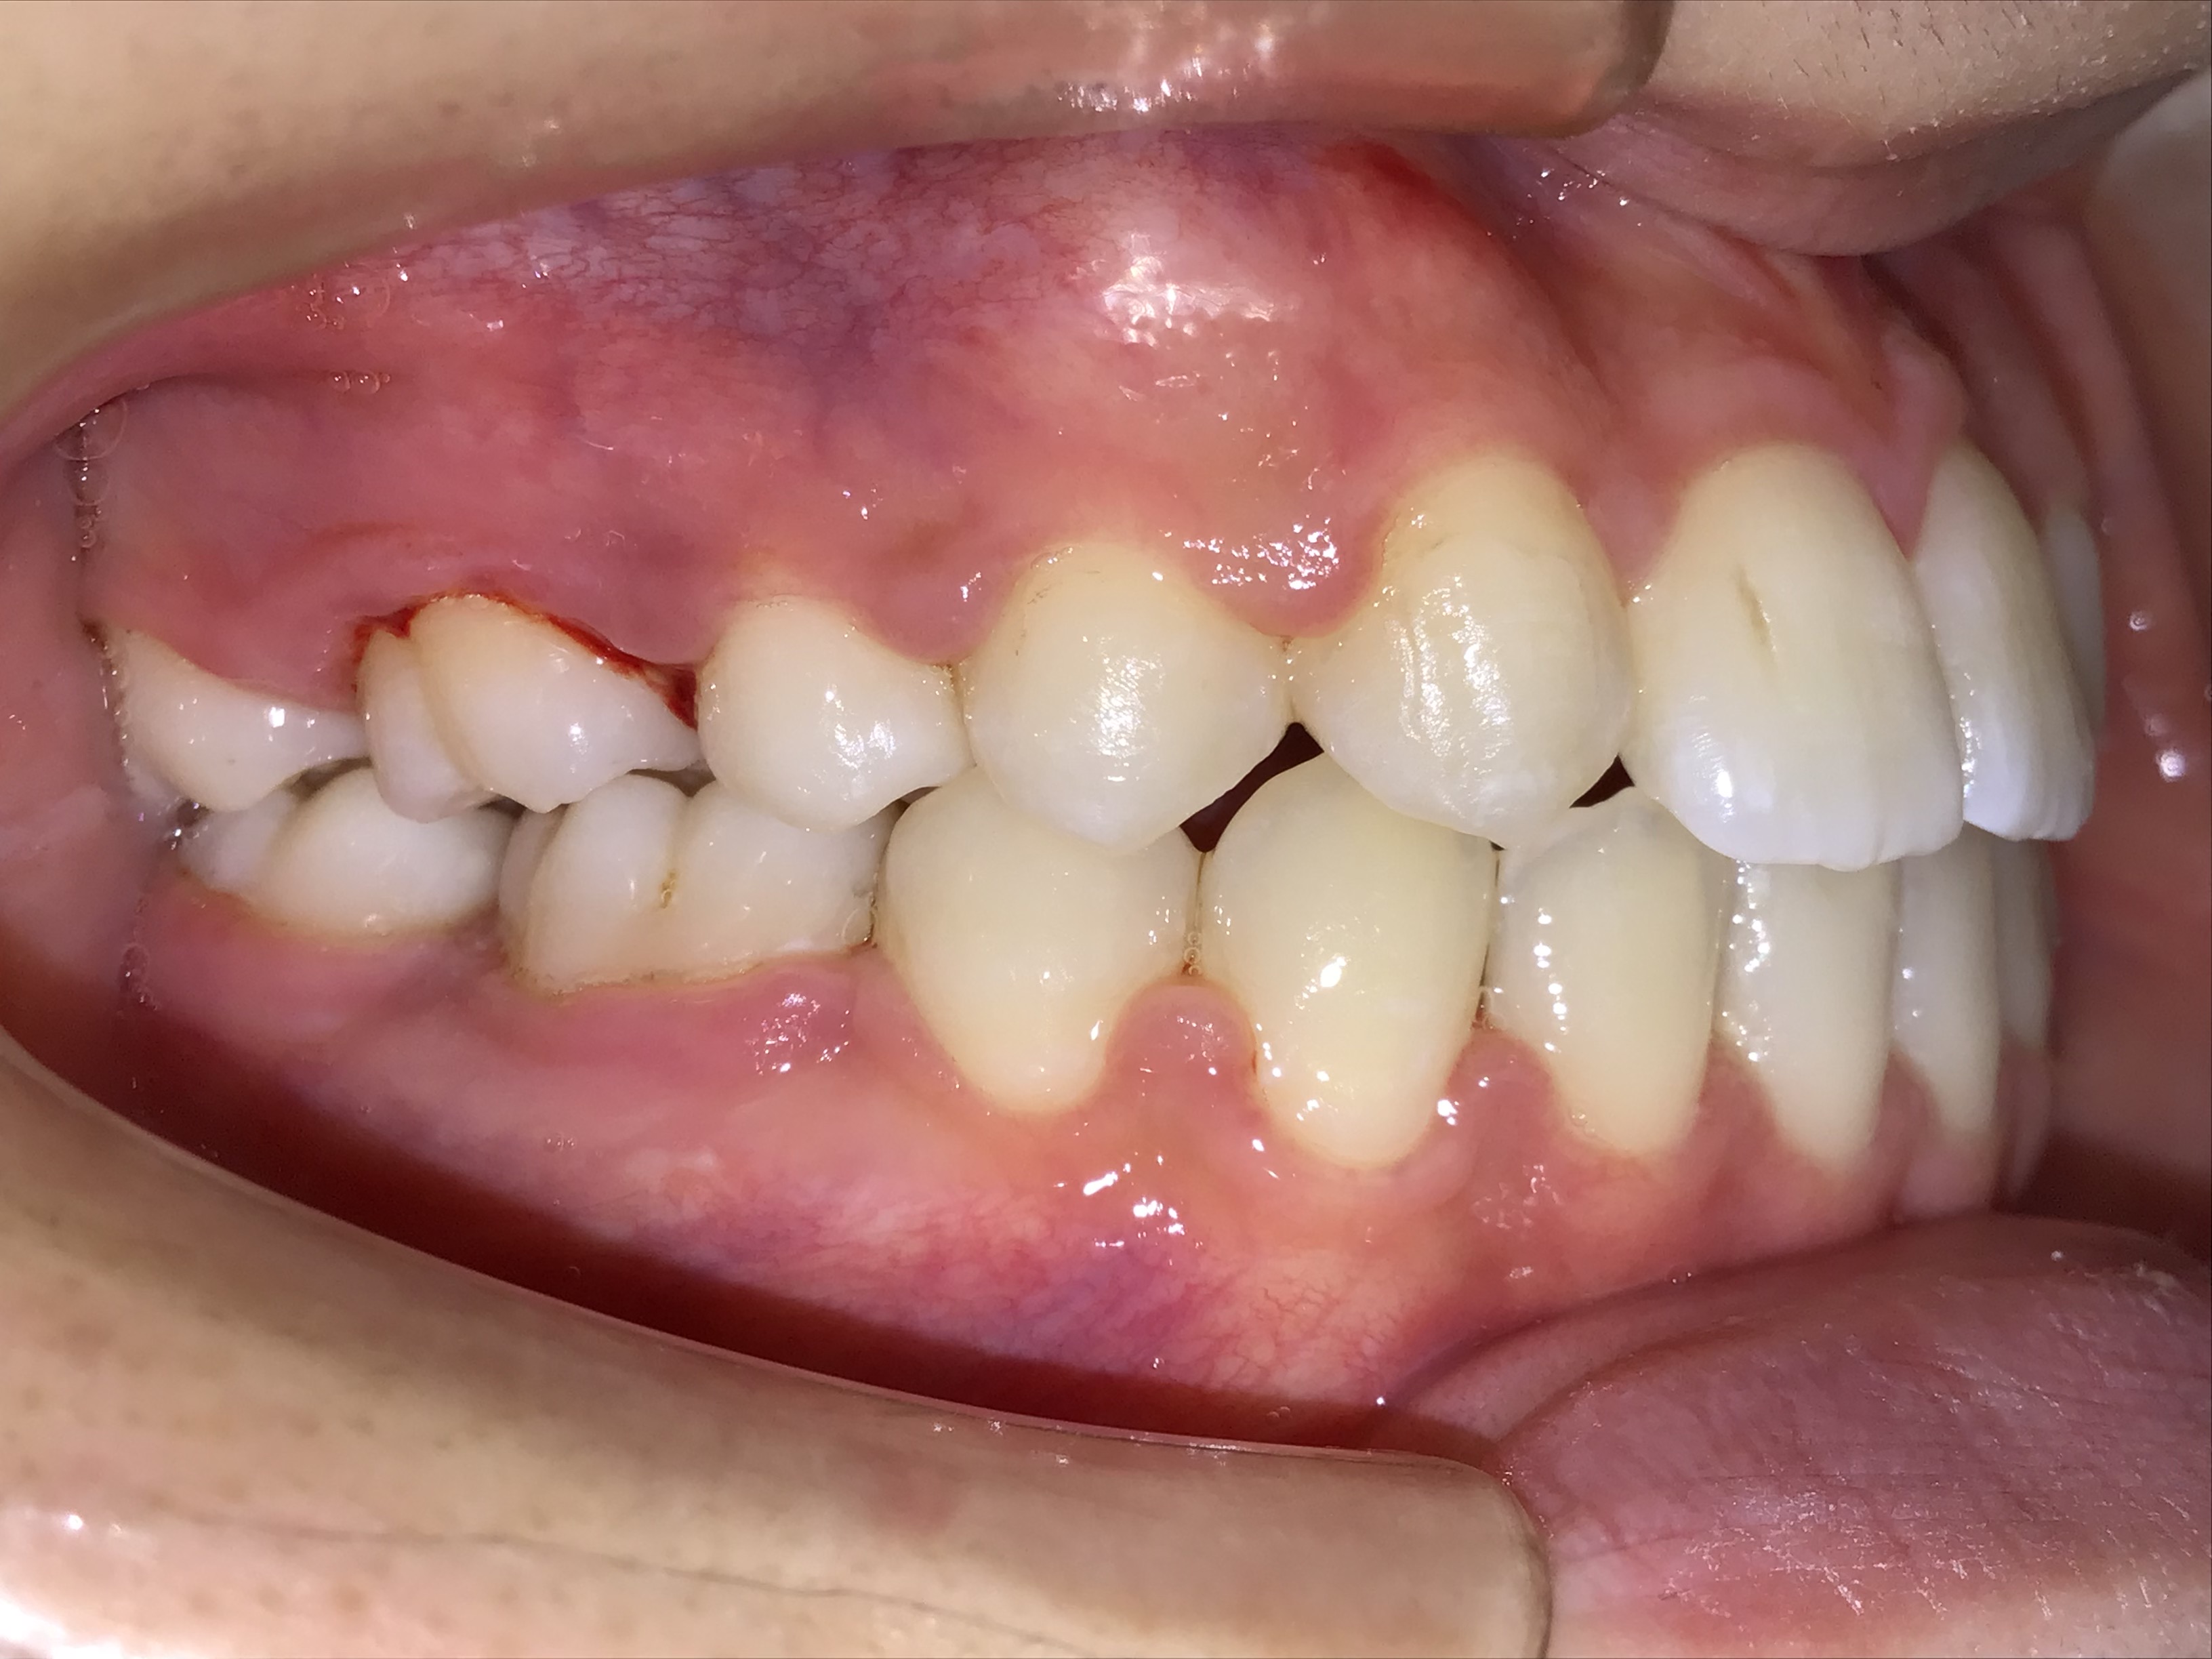

治療前 治療後 | 主訴 | 上の歯が出ている |

| 診断 | 叢生を伴う上顎前突症 |

| 初診時年齢 | 7歳10ヶ月 |

| 治療種別 | 1次矯正、2次矯正 |

| 外科処置 | 上顎左右第一小臼歯の抜歯 |

| 主な治療装置 | 歯列弓拡大装置、マルチブラケット装置など |

| 治療期間 | 1次矯正11ヶ月、2次矯正2年1ヶ月 |

| 治療費 | 1次矯正40万円(税別)、2次矯正50万円(税別) |

| リスク・副作用 | 矯正装置による不快感や痛みが生じることがあります(数日〜1、2週間で慣れることが多いです)。歯の動き方には個人差があり、予想された治療期間が延長する可能性があります。歯を動かすことにより歯根が吸収して短くなることや、歯ぐきがやせて下がることがあります。治療中は装置が付いているため歯が磨きにくくなり、むし歯や歯周病のリスクが高まります。治療途中に金属等のアレルギー症状が出ることがあります。顎関節症状(音が鳴る、あごが痛い、口が開けにくい)が出ることがあります。装置を外す時にエナメル質に微小な亀裂が入る可能性があります。装置が外れた後、保定装置を指示通り使用しないと後戻りが生じる可能性があります。 |